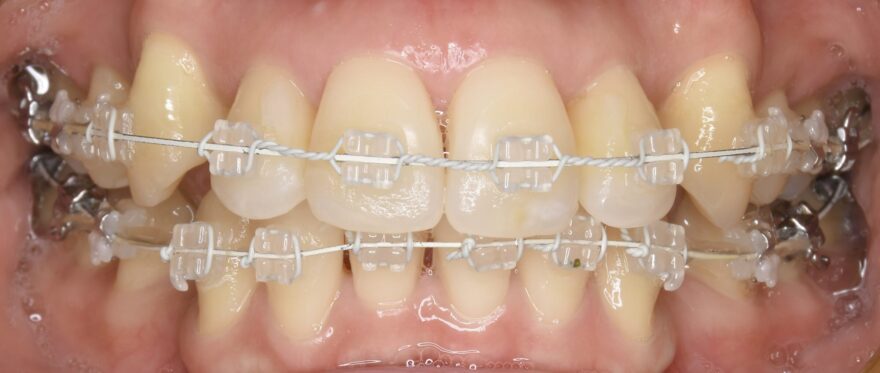

治療中の口腔内写真

上下ともには表側に矯正装置が付いています。

金属ワイヤーの外側にのみ白いコーティングがされていることが分かります。